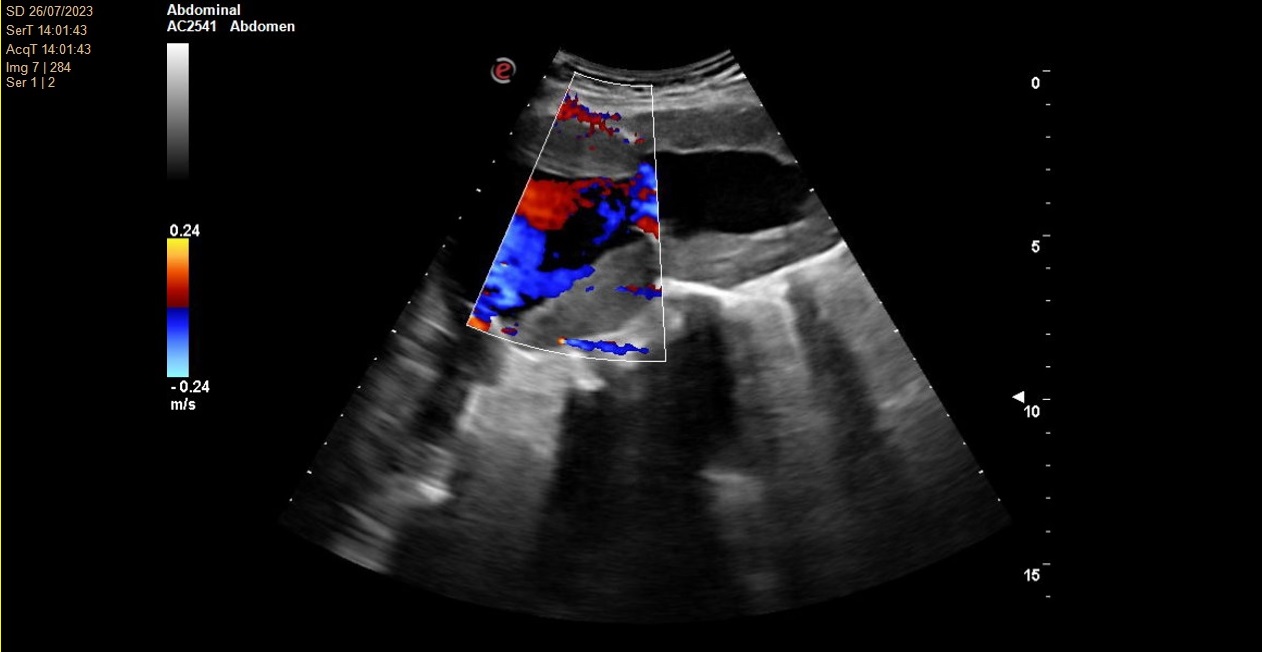

No se consigue visualizar el lóbulo hepático izquierdo ni páncreas por interposición de gas intestinal. Lóbulo hepático derecho de ecogenicidad y ecoestructura normal. Vesícula biliar de paredes finas y lisas sin contenido en su interior. Vía biliar no dilatada. Se visualiza una arteria aorta a nivel abdominal de un tamaño de 78 x 77 mm en su diámetro máximo.

Angio TC toracoabdominal en el que se observa una dilatación aneurismática de 73,8 mm de morfología fusiforme infrarenal hasta bifurcación ilíaca con trombosis mural concéntrica en toda su extensión.

Aneurisma de aorta abdominal.